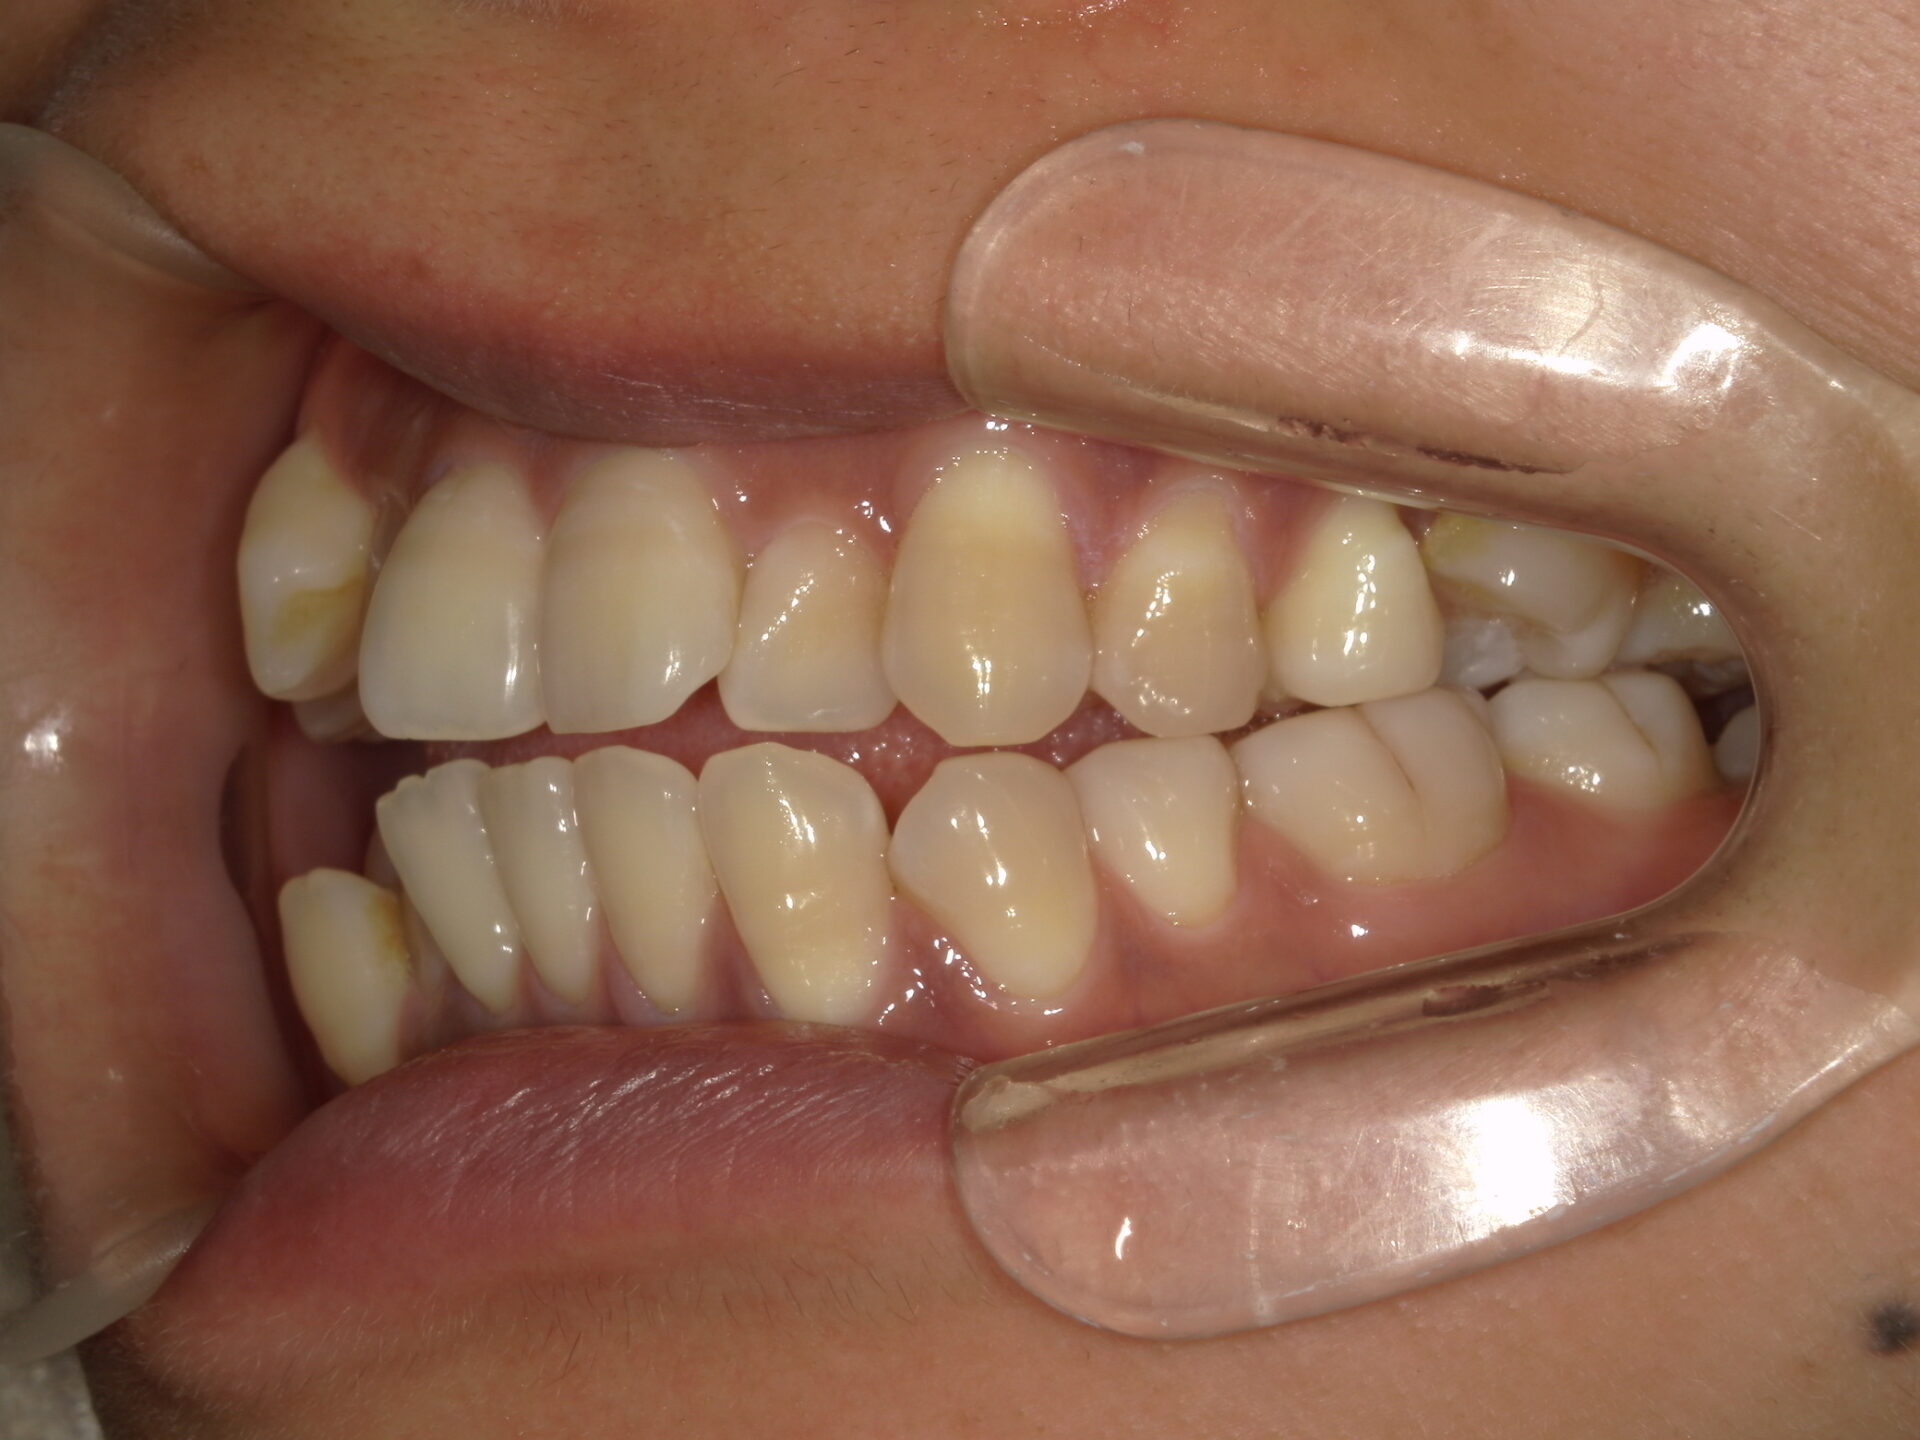

after

患者さんの年齢 20代 女性 症状 ガタガタを治したい 治療内容 マウスピース矯正治療 費用 90万(税抜) 治療期間・回数 治療期間2年、通院回数10回 メリット 笑顔が綺麗 デメリット・リスク 期間がかかることがある - マウスピース矯正